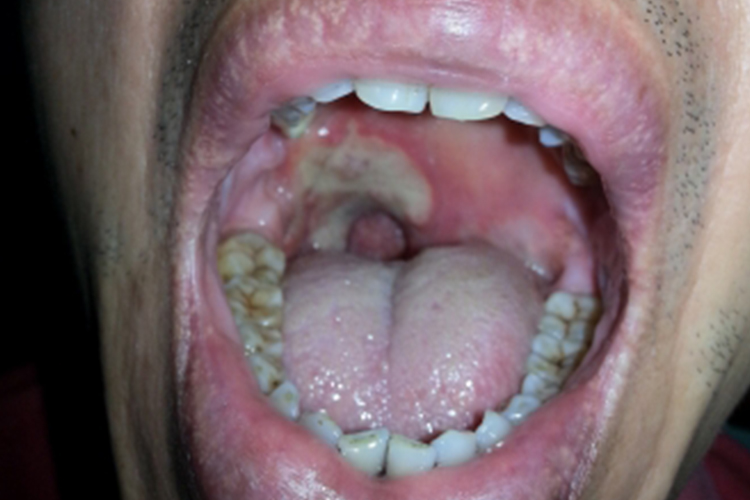

樊尚咽峡炎

樊尚咽峡炎主要症状是单侧咽痛伴有全身不适或低热,常有口臭、舌苔厚。可见一侧扁桃体病变处覆有黄色或灰白色的假膜,易于拭去,拭去后溃疡面上有小出血点。患侧下颌角淋巴结常肿大、有触痛。